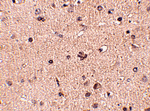

Immunohistochemistry of Slitrk2 in human brain tissue with Slitrk2 antibody at 2.5 ug/mL.